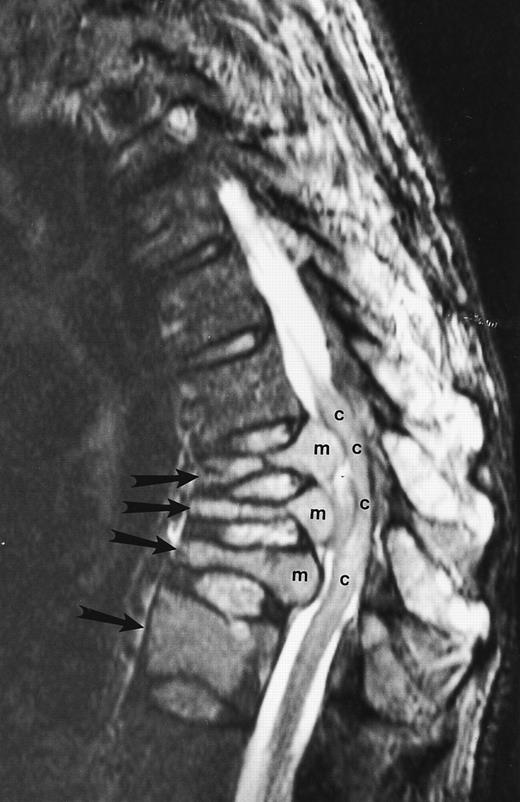

An 82-year-old man with multiple myeloma and cord compression. T2-weighted, fat-suppressed fast spin echo (5000/96, TR/TE, ET16) sagittal MR image of the thoracic spine shows abnormal signal in several compressed vertebral bodies (arrows). The spinal cord (c) is severely compressed by epidural mass (m).